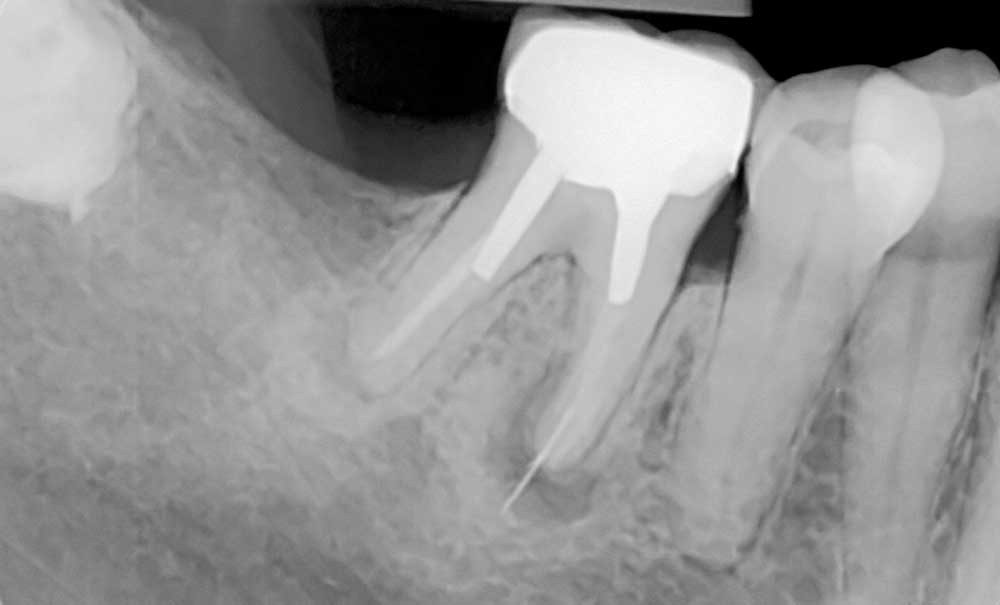

Les techniques opératoires de conservation et d’extraction des dents font partie de l’arsenal thérapeutique de tous les chirurgiens-dentistes. En revanche, la méthodologie pour répondre à la question « conserver ou extraire » n’est pas la même pour tous. Dès lors la capacité d’un praticien à répondre à cette question semble se faire sur la base de ce que l’on nomme, de manière assez vague, le sens clinique. Le but de cet article est, au travers d’éléments choisis de bibliographie et de situations cliniques, d’élargir les critères décisionnels classiques de conservation ou d’extraction d’un organe dentaire au-delà des seuls aspects biologiques habituellement décrits (parodontaux, structurels et endodontiques), en déterminant des éléments loco-régionaux puis globaux pouvant permettre de consolider la rationalité de la décision et de l’inscrire dans la relation de confiance entre le praticien et le patient.